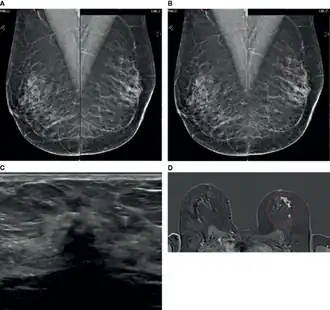

Le diagnostic de cancer lobulaire par examen physique peut être difficile car les patientes présentent souvent des signes cliniques limités et n'ont pas toujours de masse mammaire palpable ; les signes peuvent être souvent vagues, comme un épaississement de la peau ou une sensation de capitonnage de la peau. La mammographie et l'échographie du sein ont une faible sensibilité pour détecter le cancer lobulaire par rapport aux autres tumeurs invasives du sein. Cette difficulté peut être largement attribuée au modèle de croissance infiltrante diffuse de ce type de cancer.

Mammographie

La mammographie est considérée comme la méthode d'imagerie de référence » pour la détection précoce du cancer du sein , avec une sensibilité allant généralement de 63 % à 98 %. Ceci est réalisé en produisant des images haute résolution, mettant en évidence les différences de contraste entre les tissus mammaires sains et malins [26]. La détection de cancer lobulaire par mammographie est notoirement difficile en raison du modèle de croissance tumorale infiltrant qui ne détruit pas les structures anatomiques sous-jacentes et ne provoque pas de réaction stromale. En raison de ces caractéristiques tumorales , la sensibilité de détection du cancer lobulaire par mammographie est beaucoup plus faible, comprise entre 57 % et 81 %. Les faux positifs ne sont pas non plus rares, avec des taux rapportés allant de 8 % à 24 % [27]. Le taux de faux négatifs dans le diagnostic de cancer lobulaire est beaucoup plus élevé que celui des autres cancers du sein invasifs [28]. Plus de la moitié des mammographies jugées ne montrant aucun signe de malignité se sont ensuite révélées évocatrices d’une tumeur.

La relation inverse entre la densité du tissu mammaire et la sensibilité mammographique est bien établie. Dans le cas de tissu mammaire extrêmement dense, la détection mammographique peut être aussi faible que 30 % [26]. Dans une étude [29] la sensibilité mammographique s'est avérée être d'environ 34 % dans les cas de cancer lobulaire et, après ajustement pour les patientes présentant un tissu mammaire dense, la sensibilité a diminué à seulement 11 %. En plus de son schéma de croissance histologique distinct, une faible opacité peut également expliquer les difficultés liées à l'identification clinique de cancer lobulaire par mammographie [30]. Une autre étude [31] rapporte que jusqu'à 50 % des cancers lobulaires présentent un manque d'opacité inférieur ou égal au tissu mammaire normal lors de l'imagerie. Ce manque de contraste met en évidence la difficulté de délimiter les tissus mammaires malins du cancer lobulaire et normaux à l'aide de la mammographie conventionnelle [26]. Les carcinomes invasifs sont souvent associés à des masses spiculées de haute densité, dues à la perturbation de l'architecture normale du tissu mammaire. Ce type de masse peut être facilement détecté par mammographie. Les rapports suggèrent que le cancer lobulaire se manifeste par des lésions mal spiculées et mal définies, avec une masse bien définie observée dans moins de 1 % des cas [26]. De plus, jusqu'à 35 % des cancers lobulaires ne seraient visibles que sur la vue craniocaudale [27]. Cela peut également contribuer à rendre les estimations de la taille et de l’étendue de la tumeur moins fiables [32]. Les microcalcifications sont souvent considérées comme des indicateurs courants d'une maladie du sein et sont facilement détectées par mammographie, mais la probabilité qu'un cancer lobulaire produise des calcifications est faible [33]. La présence de calcifications associées au cancer lobulaire varierait entre 1 % et 28 %. Il s’agit d’une autre caractéristique distinctive du cancer lobulaire qui contribue à l’incapacité de la mammographie à détecter facilement ces tumeurs [26].

Échographie

L’échographie est l'imagerie diagnostique du sein le plus couramment utilisé en conjonction avec la mammographie. L’échographie était à l’origine utilisée comme outil permettant de différencier les lésions solides des lésions kystiques et de guider les biopsies [34]. Cependant, grâce aux progrès technologiques, l’échographie a désormais amélioré sa sensibilité pour distinguer les lésions bénignes des lésions malignes et est utilisée dans l’investigation de toutes les masses palpables du sein [26]. La relation entre la densité mammaire et la sensibilité de la mammographie est bien documentée, mais avec l'ajout de l'échographie, la détection des cancers asymptomatiques, qui incluent souvent le cancer lobulaire, pourrait augmenter jusqu'à 40 % [30]. La sensibilité rapportée de l'échographie dans la détection du cancer lobulaire varie de 68 % à 98 % [26],[35]. Les caractéristiques échographiques les plus courantes du le cancer lobulaire sont une masse irrégulière et hypoéchogène avec des marges mal définies et des ombres postérieures, observées dans jusqu'à 61 % des cas [36]. Des masses bien circonscrites sont rarement observées dans les tumeurs lobulaires, se manifestant dans seulement 2 à 12 % des cas [26].

En comparant la sensibilité de l’échographie à celle de la mammographie, il semblerait que la première soit un outil d’imagerie plus précieux pour la détection du cancer lobulaire. Une étude a révélé que des faux négatifs se produisaient dans 29,9 % des cas lors de l'utilisation de la mammographie, tandis que l'échographie avait une sensibilité de 97,8 % pour la détection [37]. L'utilisation de l'échographie s'est avérée utile pour améliorer considérablement la détection de l'ILC [34].

Imagerie à résonance magnétique

L'imagerie par résonance magnétique (IRM) est principalement utilisée dans le dépistage des cancers du sein à haut risque, pour évaluer et comparer les résultats de la mammographie et de l'échographie, pour évaluer la réponse à la chimiothérapie et pour évaluer les tumeurs du sein homolatérales et controlatérales. L'IRM a une sensibilité globale élevée de 90 % pour la détection des cancers du seine et une sensibilité de 93 % pour la détection du cancer lobulaire [26]. Ce niveau élevé de sensibilité est basé sur les niveaux accrus de néovascularisation dans les tumeurs, car celles-ci créent constamment de nouveaux vaisseaux sanguins dans le but de fournir des nutriments nécessaires à la croissance ultérieure de la tumeur. Cela entraîne une absorption rapide du produit de contraste à base de gadolinium, qui peut s'accumuler dans le stroma du cancer du sein [38]. Cette sensibilité élevée s’étend également à la détection accrue des maladies multifocales, multicentriques et controlatérales [39]. L'IRM détecte des foyers tumoraux supplémentaires et une maladie du sein controlatéral chez 16 % à 58 % des patientes atteintes de cancer lobulaire, non détectées lors de la mammographie initiale [40]. Une étude de a conclu que les patients atteints de cancer lobulaire étaient deux fois plus susceptibles de voir leur schéma thérapeutique modifié à la suite de l'IRM que les patients de tout autre sous-type histologique [40]. Malgré son haut niveau de sensibilité dans la détection précoce du cancer du sein, l'une des limites considérables de l'IRM est le manque de spécificité [41]. Une faible spécificité peut entraîner un traitement excessif des patients, entraînant une intervention chirurgicale étendue sans bénéfice clinique supplémentaire [39].

Malgré cela, l'amélioration présumée des résultats chirurgicaux et de la survie sans récidive grâce à l'IRM est discutée. Une étude rétrospective [42] a évalué l’impact de l’IRM sur les taux de reprise chirurgicale pour résection insuffisante de la tumeur et a conclu que les patients ayant subi une IRM avant la chirurgie présentaient des taux de de reprise chirurgicale significativement inférieurs (9 %) à ceux n’ayant pas subi d’IRM (27 %). Cette étude a également révélé que l’évaluation par IRM n’entraînait pas un nombre plus élevé de mastectomies. D'autre part, plus récemment, une méta-analyse de l'IRM préopératoire sur les résultats chirurgicaux a rapporté que l'IRM augmentait de manière significative le taux de mastectomie dans tous les sous-types de cancer du sein et a trouvé des preuves faibles pour étayer l'affirmation selon laquelle l'IRM peut réduire les taux de reprise chirurgicale dans patients atteints de cancer lobulaire [43]. Par conséquent, on ne peut pas affirmer avec certitude que l’utilisation de l’IRM réduit le taux de récidive ou de survie globale sans récidive dans la cas de cancer lobulaire [26]. Dans l’ensemble, l’IRM est particulièrement avantageuse par rapport aux méthodes d’imagerie standard en raison de sa sensibilité accrue dans la détection des cancers lobulaires et de l’amélioration de la détection des tumeurs homolatérales et controlatérales. Malgré ses limites, l’IRM fournit des informations diagnostiques supplémentaires qui peuvent manquer lors de l’imagerie standard et doit être utilisée en association avec l’échographie et la mammographie pour évaluer avec précision les patients atteints de cancer lobulaire [26],[39].